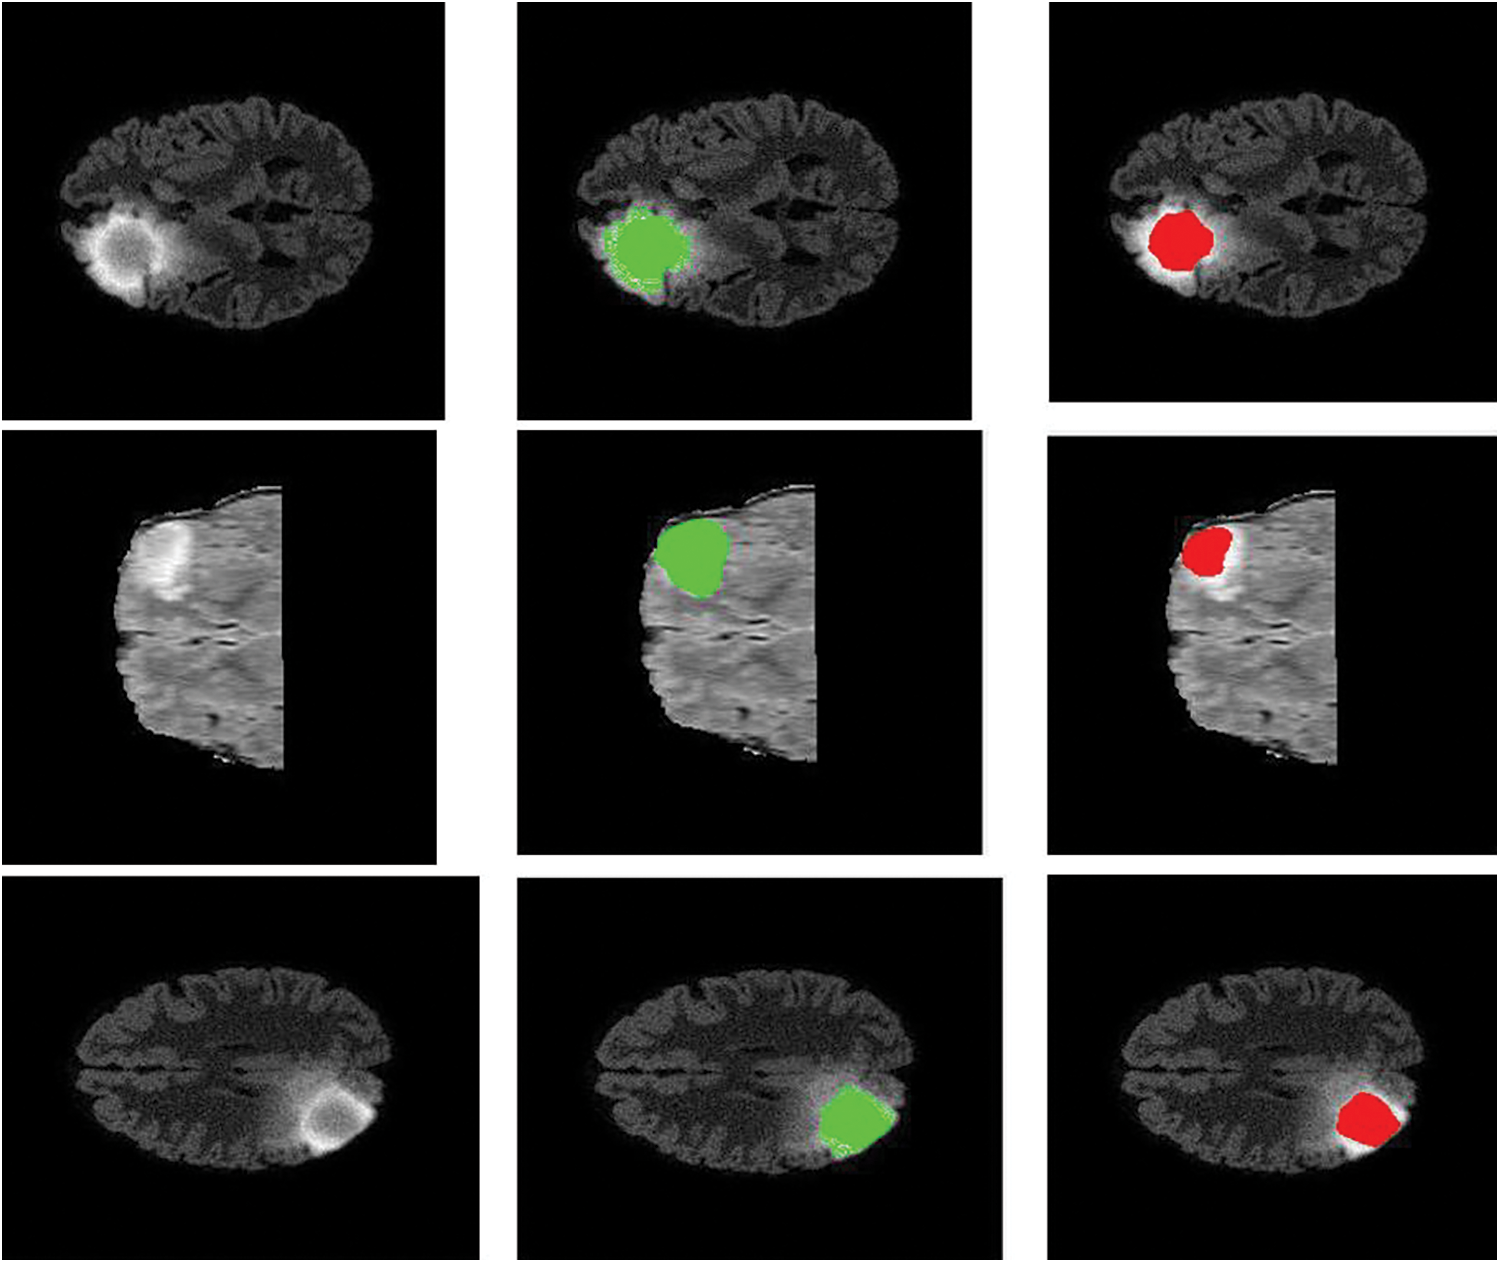

The intratumor structures of edema, necrotic, enhancing tumor and nonenhancing tumor core have been clustered into regions of: The enhancing tumor region (ET) which contains entire tissues of tumor. (b) The tumor core region (TC) is used to enhance tumor, non-enhancing tumor core and necrotic. (c) The whole tumor region (WT). Sample visualization of the results attained are demonstrated in Figs. 6 and 7.

Figure 7: Sample visualization resutls (The first column shows the input image, second column represnets the Edema region, and thrid column denotes the Enhancing region)